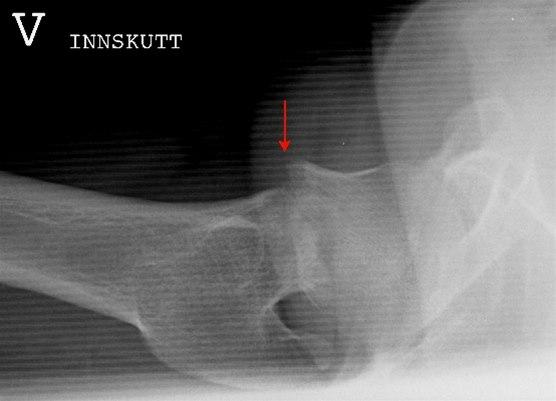

Halvparten av alle hoftebrudd utgjøres av brudd gjennom lårhalsen, brudd i lårbeinsknuten utgjør 45 prosent, og brudd rett under lårbeinsknuten utgjør 5%. Bruddene inndeles etter hvor lårbeinet brekker samt undertyper . Bildene under viser lårhalsbrudd og skillet mellom brudd med og uten feilstilling (dislosering).

Ikke alle brudd fører til knekkdannelse mellom de to bruddendene. Det hender også at bruddet fører til at de to beinendene stukes sammen (innkilte brudd) slik at bruddet er forholdsvis stabilt og ikke kommer ut av stilling. Slike brudd kan være vanskelige å se på røntgen.